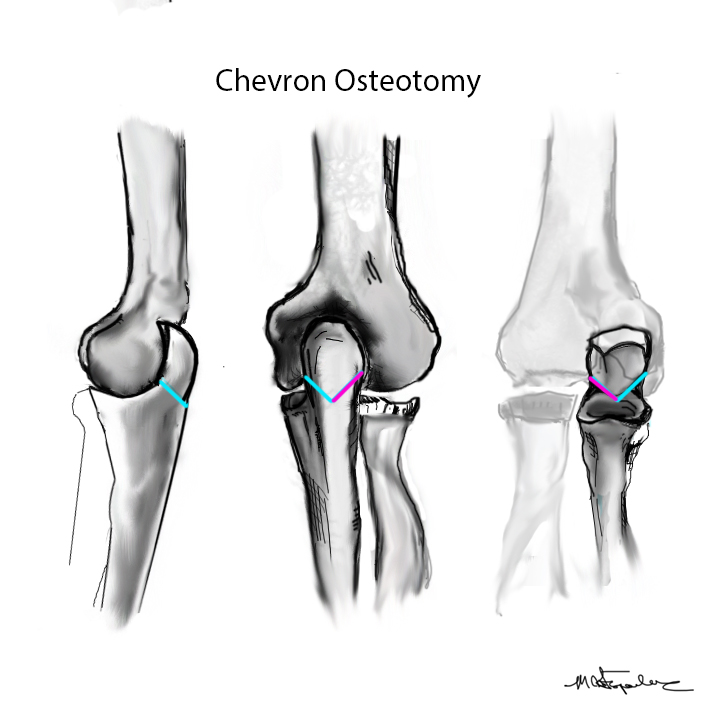

Olecranon Osteotomy

Technique

AO foundation surgery reference Chevron osteotomy

Chevron

- distally based V shaped

- through bare area of olecranon / smallest width of greater sigmoid notch

- 3 cm from tip

Fixation

- TBW v plate v intramedullary screw